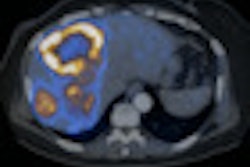

In-111-DTPA-octreotide scan (A) demonstrates recurrent mesenteric nodule (arrow) on the anterior view in a patient with a midgut carcinoid tumor resected five years previously, with no other tumor seen with planar imaging or SPECT/CT (B). Ga-68 DOTATATE PET/CT anterior 3D maximum intensity projection (C) and axial fused images (D) show other metastases (arrows), changing the surgical plan for resection. Findings were verified at surgery. Image courtesy of Dr. Ronald C. Walker.On the downside, the U.S. Food and Drug Administration (FDA) has yet to approve Ga-68 DOTATATE PET/CT to diagnose, stage, or help determine treatment for patients with neuroendocrine tumors. As a result, there is no reimbursement for the procedure.